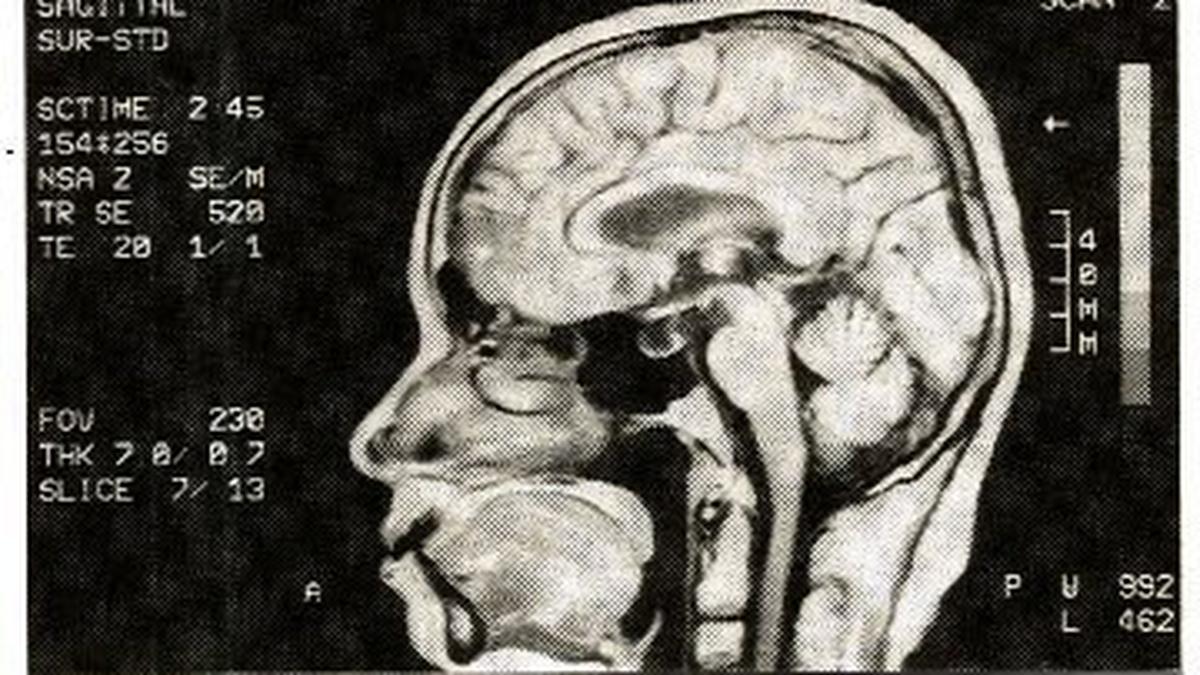

• Neurobiological Factors => Research involves irregularities in certain brain regions, particularly the basal ganglia, and the functioning of neurotransmitters like dopamine and serotonin.